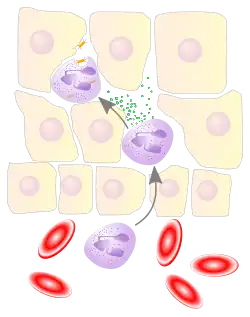

Воспалённые или повреждённые участки соединительной ткани требуют немедленной миграции разнообразных лейкоцитов, в том числе нейтрофилов, в очаг повреждения для удаления патогенных микроорганизмов и восстановления ткани. Наиболее хорошо процесс миграции в ткани изучен для нейтрофилов, которые прибывают в очаг воспаления первыми, существенно быстрее моноцитов, и способны развивать защитные метаболические реакции (в частности, «окислительный взрыв», сопровождающийся продукцией активных форм кислорода) в течение секунд. Активация нейтрофилов сопровождается в первую очередь высвобождением содержимого секреторных гранул. При развитии локального воспаления макрофаги, активированные бактериями или повреждениями ткани, выделяют провоспалительные цитокины, такие как IL-1 или фактор некроза опухоли α (TNF-α). Также к факторам хемотаксиса нейтрофилов относят компоненты комплемента, вещества, выделяемые тучными клетками, иммунные комплексы, эндотоксины и бактериальные пептиды, а также наполненные лизосомы, выходящие в ткань при распаде погибших нейтрофилов и макрофагов[33]. Под действием провоспалительных цитокинов в эндотелиальных клетках, выстилающих ближайшие к очагу воспаления посткапиллярные венулы, увеличивается количество селектинов на поверхности, обращённой в просвет сосуда. Нейтрофилы, циркулирующие в посткапиллярных венулах и имеющие подходящий набор поверхностных гликопротеинов, связываются с селектинами на поверхности эндотелиальных клеток. На данном этапе связывание с эндотелием непрочное, и нейтрофилы продолжают «катиться» по поверхности эндотелия. Провоспалительные цитокины запускают экспрессию интегринов в катящихся нейтрофилах и лигандов интегринов, известных как ICAM-1, на поверхностях эндотелиальных клеток. В то же время межклеточные контакты между клетками эндотелия ослабляются, и эндотелий становится более проницаемым. За счёт интегринов нейтрофилы прочно связываются с эндотелием и прекращают качение, и в конечном счёте приступают к прохождению через эндотелий с помощью псевдоподий (этот процесс известен как диапедез). Проникновение нейтрофилов через эндотелий облегчается благодаря длинному и сегментированному ядру. Прохождение нейтрофилов через эндотелий и дальнейшая миграция к очагу воспаления стимулируются хемокинами[34]. Базальные мембраны нейтрофилы преодолевают благодаря выделению содержимого желатиназных гранул[35].

Активированные нейтрофилы при встрече с микроорганизмами поглощают их с помощью псевдоподий, и микроорганизм оказывается внутри фагосомы. В течение нескольких секунд после активации нейтрофила изменяется его мембранный потенциал, в клетку входят ионы натрия и кальция, изменяется текучесть мембраны[33]. Примерно через 30 секунд после поглощения частицы специфические гранулы сливаются с фагосомой, изливая в неё своё содержимое, после чего фагосома дополнительно закисляется с помощью мембранных протонных помп. С закисленными фагосомами сливаются азурофильные гранулы (примерно через 1—3 минуты после поглощения частицы). В ходе фагоцитоза в нейтрофиле образуются активные формы кислорода, такие как супероксид-анион и перекись водорода, и другие компоненты гранул с бактерицидными свойствами. Активные формы кислорода используются для уничтожения бактериальной клетки, наряду с содержимым специфических и азурофильных гранул. Белок лактоферрин, входящий в состав специфических гранул, не убивает бактерию напрямую, а прочно связывает ионы железа, делая их недоступными для бактерии и, в результате, приводя к её смерти. Содержимое гранул (в частности, азурофильных) может высвобождаться в ходе дегрануляции, после которой восстановления гранул не происходит. Комбинация описанных механизмов способна убить практически любую бактерию, и погибшие бактериальные клетки впоследствии расщепляются лизосомными ферментами. Наиболее чувствительны к компонентам гранул нейтрофилов дрожжи (Candida) и бактерии из числа стрептококков и стафилококков. Нейтрофилы, погибшие апоптозом, бактерии, полуразрушенные останки клеток и тканевая жидкость формируют густой гной белого или жёлтого цвета[40][35].